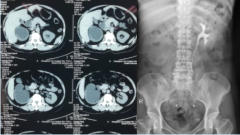

输尿管狭窄别怕,“黑科技”ALLIUM输尿管支架解困扰

患有输尿管狭窄是种什么样的体验?长期腰背部憋胀不适,发热,厌食,疾病带来的痛苦一言难尽……输尿管狭窄病因复杂,极易引起不同程度的上尿路梗阻和肾积水,甚至威胁患者生...